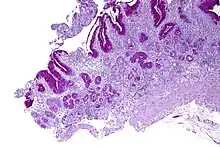

| Micrograph showing nodular enterochromaffin-like cell hyperplasia, as demonstrated with chromogranin A immunostaining, in the body of the stomach. Parietal cells are not readily apparent. These changes are in keeping with autoimmune metaplastic atrophic gastritis, a histologic correlate of vitamin B12 deficiency anemia. | |